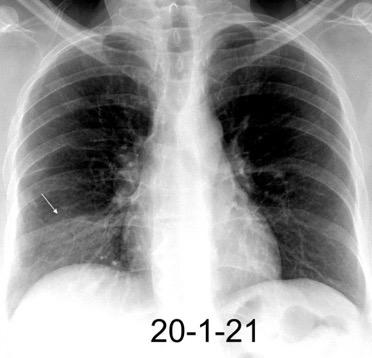

Tromboembolismo pulmonar Diafragma elevado 20%

Atelectasia crónica de LLI en paciente con enfermedad neuromuscular.